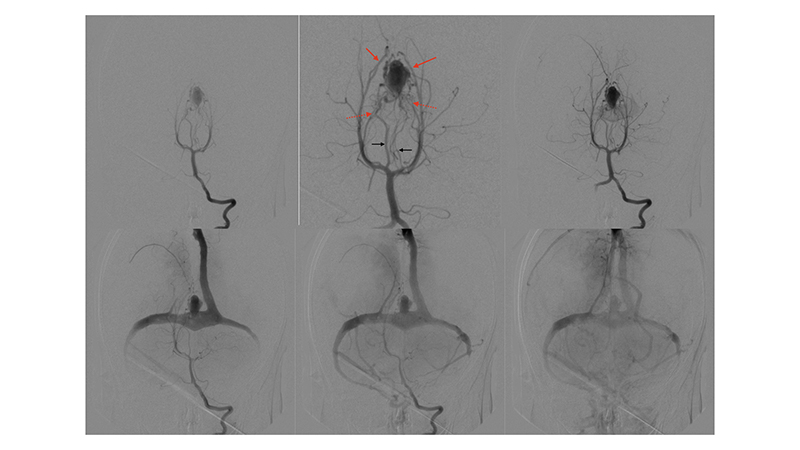

- Προσθιοπίσθια λήψη κατά την έγχυση στην δεξιά έσω καρωτίδα. Η αρτηριοφλεβώδης επικοινωνία της φλέβας του Γαληνού σκιαγραφείται από παλινδρόμηση στην δεξιά υποκλείδιο και σπονδυλική αρτηρία. Η φλεβική παροχέτευση του δεξιού εγκεφαλικού ημισφαιρίου γίνεται πολύ καθυστερημένα, λόγω απόφραξης των εγκαρσίων κόλπων αμφοτερόπλευρα (μαύρα βέλη).

- Προσθιοπίσθια λήψη κατά την έγχυση στην αριστερή έσω καρωτίδα. Η αρτηριοφλεβώδης επικοινωνία της φλέβας του Γαληνού σκιαγραφείται από την οπίσθια αναστομωτική αρτηρία. Η φλεβική παροχέτευση του αριστερού εγκεφαλικού ημισφαιρίου γίνεται πολύ καθυστερημένα, λόγω απόφραξης των εγκαρσίων κόλπων αμφοτερόπλευρα (μαύρα βέλη).

- Προσθιοπίσθια λήψη κατά την έγχυση στην αριστερή σπονδυλική αρτηρία. Ελέγχονται πολλαπλές μικροφίστουλες στο τοίχωμα της φλέβας του Γαληνού και μικρές αρτηριοφλεβώδεις επικοινωνίες στην χοριοειδή σχισμή (μικτού τύπου, τοιχωματικού και χοριοειδούς). Αρδεύονται από υποεπενδυματικούς τροφοφόρους κλάδους, εκ του Ρ1 τμήματος των οπισθίων εγκεφαλικών αρτηριών αμφοτερόπλευρα κυρίως δεξιά, που πορευόμενοι στο πλάγιο τοίχωμα της 3ης κοιλίας εκατέρωθεν, συναντούν την χοριοειδή σχισμή και εκείθεν αρδεύουν την αρτηριοφλεβώδη επικοινωνία (μαύρα βέλη). Επίσης συμμετέχουν οπισθιοπλάγιοι έσω χοριοειδείς (διακεκομμένο κόκκινο βέλος) και οπισθιοπλάγιοι έξω χοριοειδείς κλάδοι (κόκκινο βέλος) από το Ρ2 και Ρ3 τμήματα των οπισθίων εγκεφαλικών αρτηριών αμφοτερόπλευρα, που δια της χοριοειδούς σχισμής καταλήγουν στο οπίσθιο τοίχωμα της φλέβας του Γαληνού. Διακρίνεται επίσης η απόφραξη των εγκαρσίων κόλπων και η αναστροφή της ροής προς το εγκεφαλικό φλεβικό δίκτυο με συμφόρηση των εγκεφαλικών φλεβών.